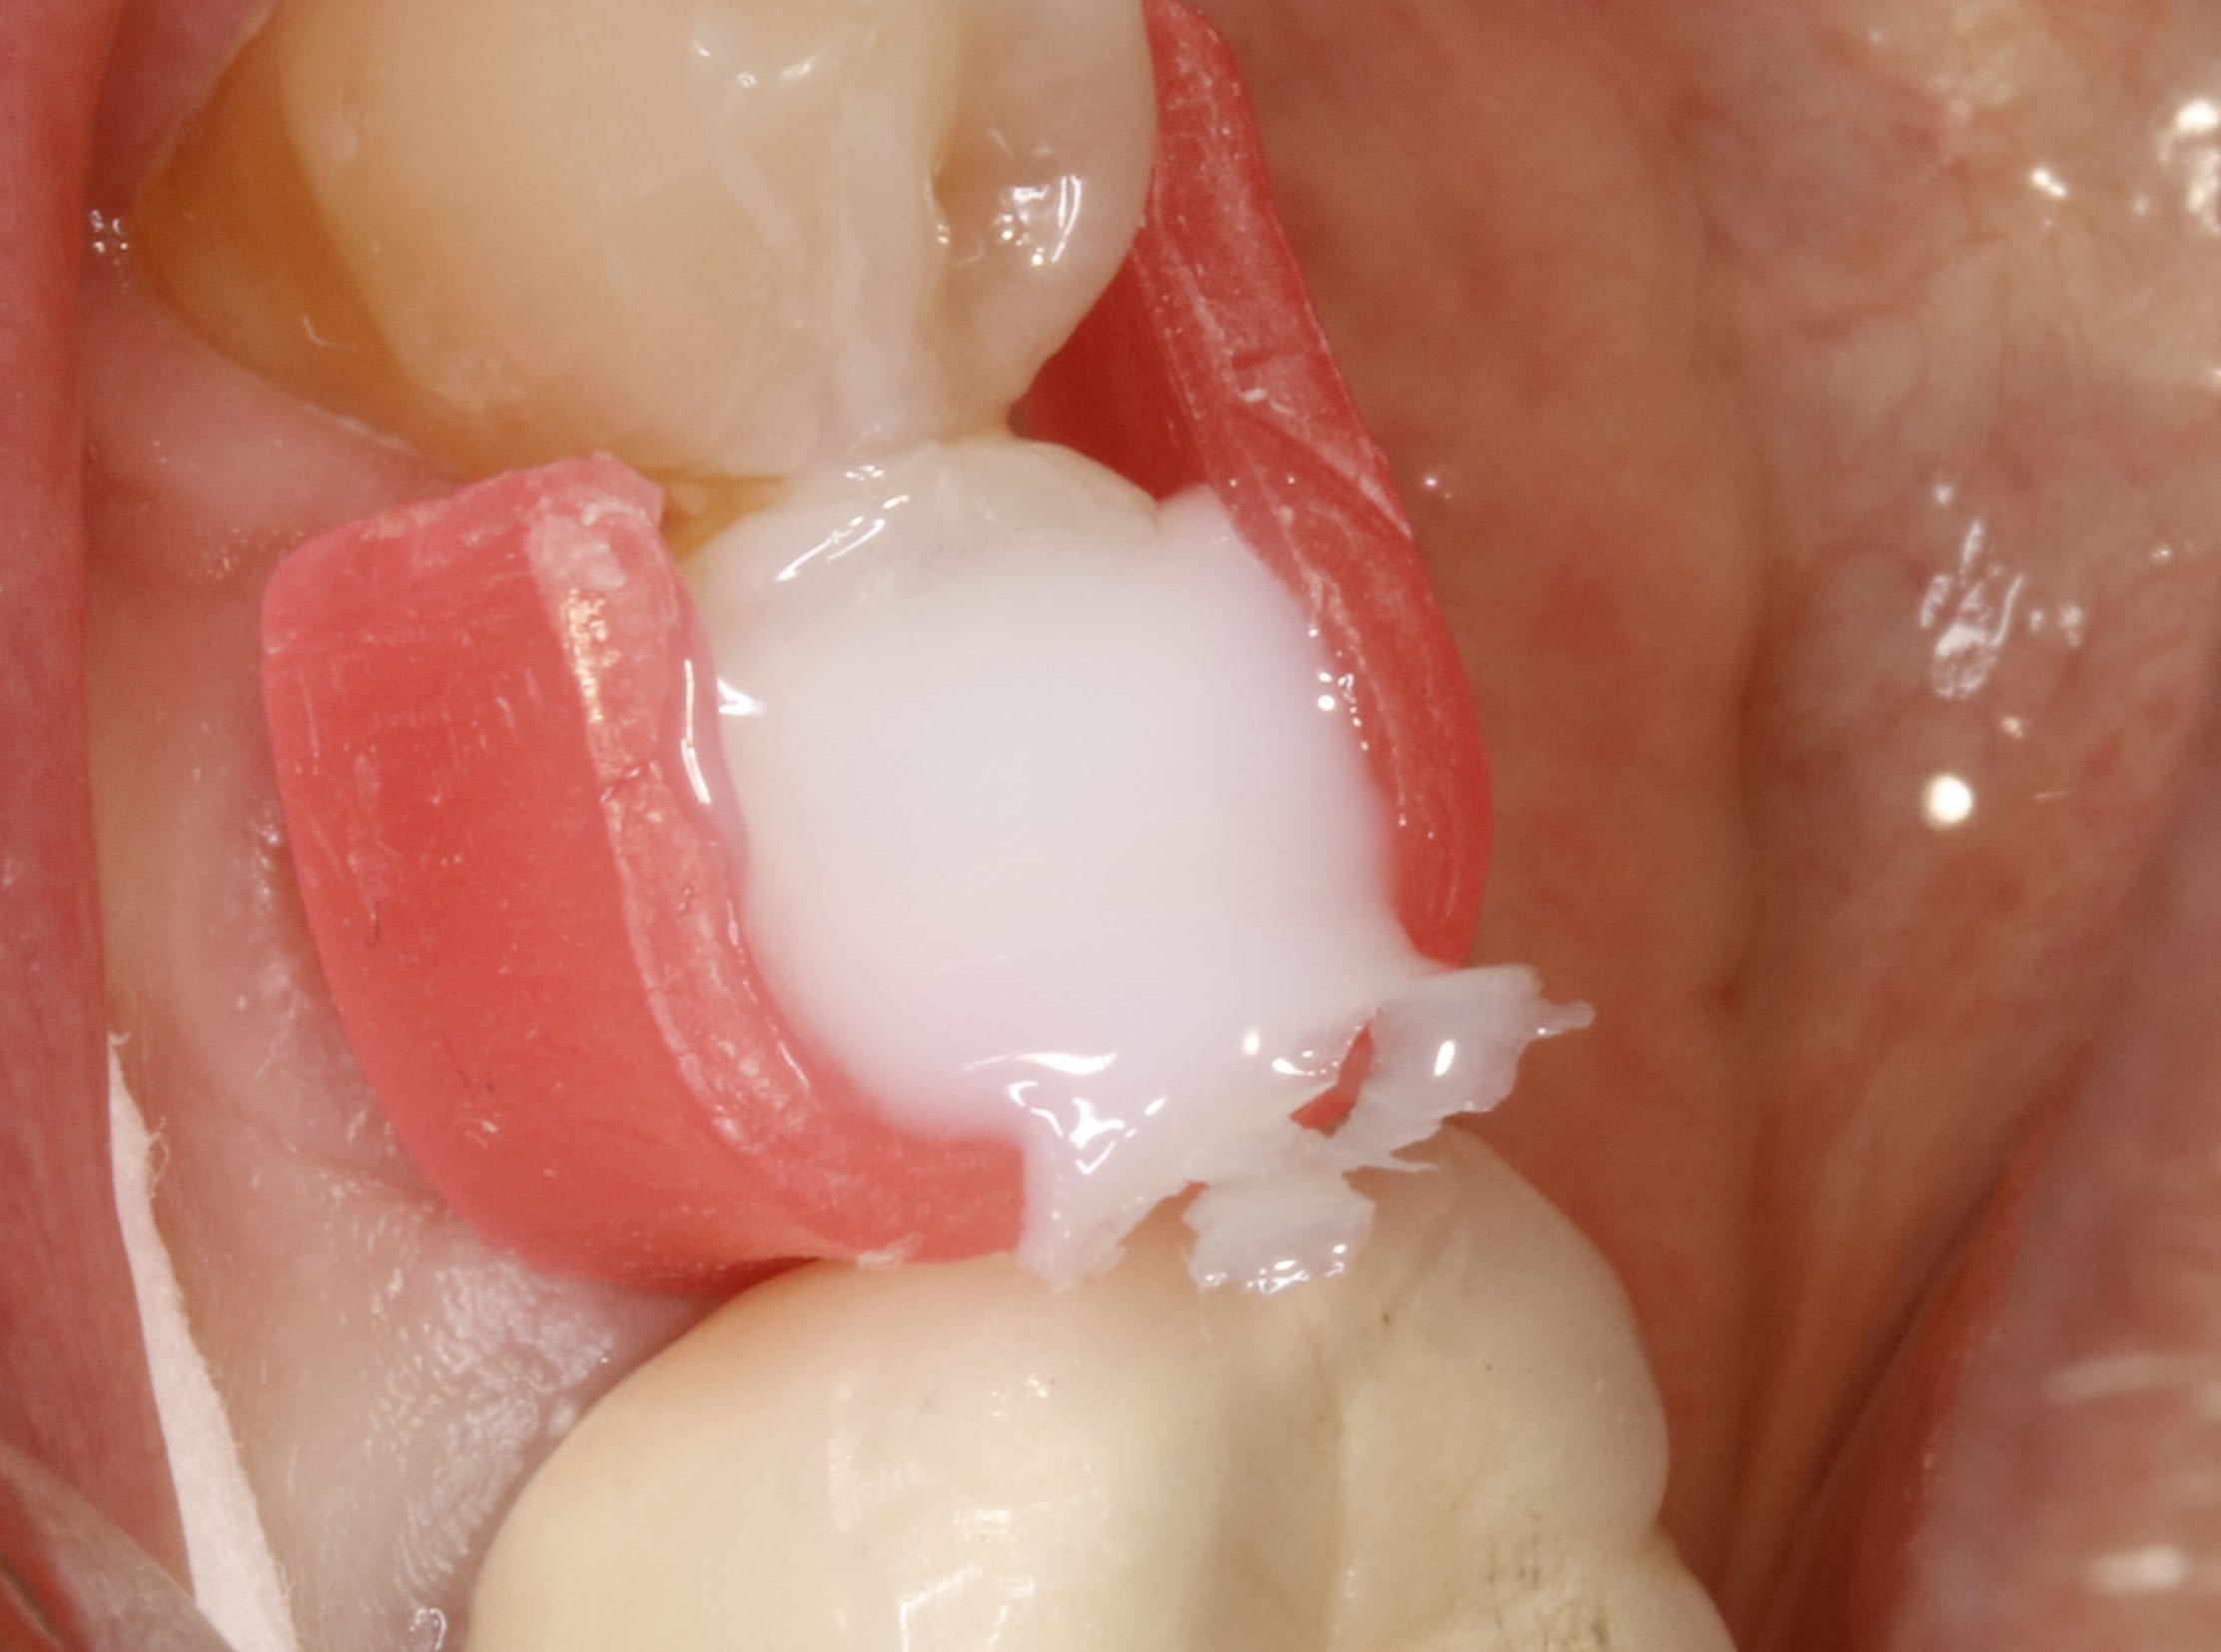

25/04/2025 à 12h42

autre truc de vieux qui va avec le screw post :

quand tu as niqué la gencive , elle a été bien brave , il ne s agit pas d aller la contrarier avec de matrices des de ci de là , la cire molle c est tres bien . tu peux l esquicher sous la limite

K8yo3krotsfkp9detl5s3w652047 - Eugenol